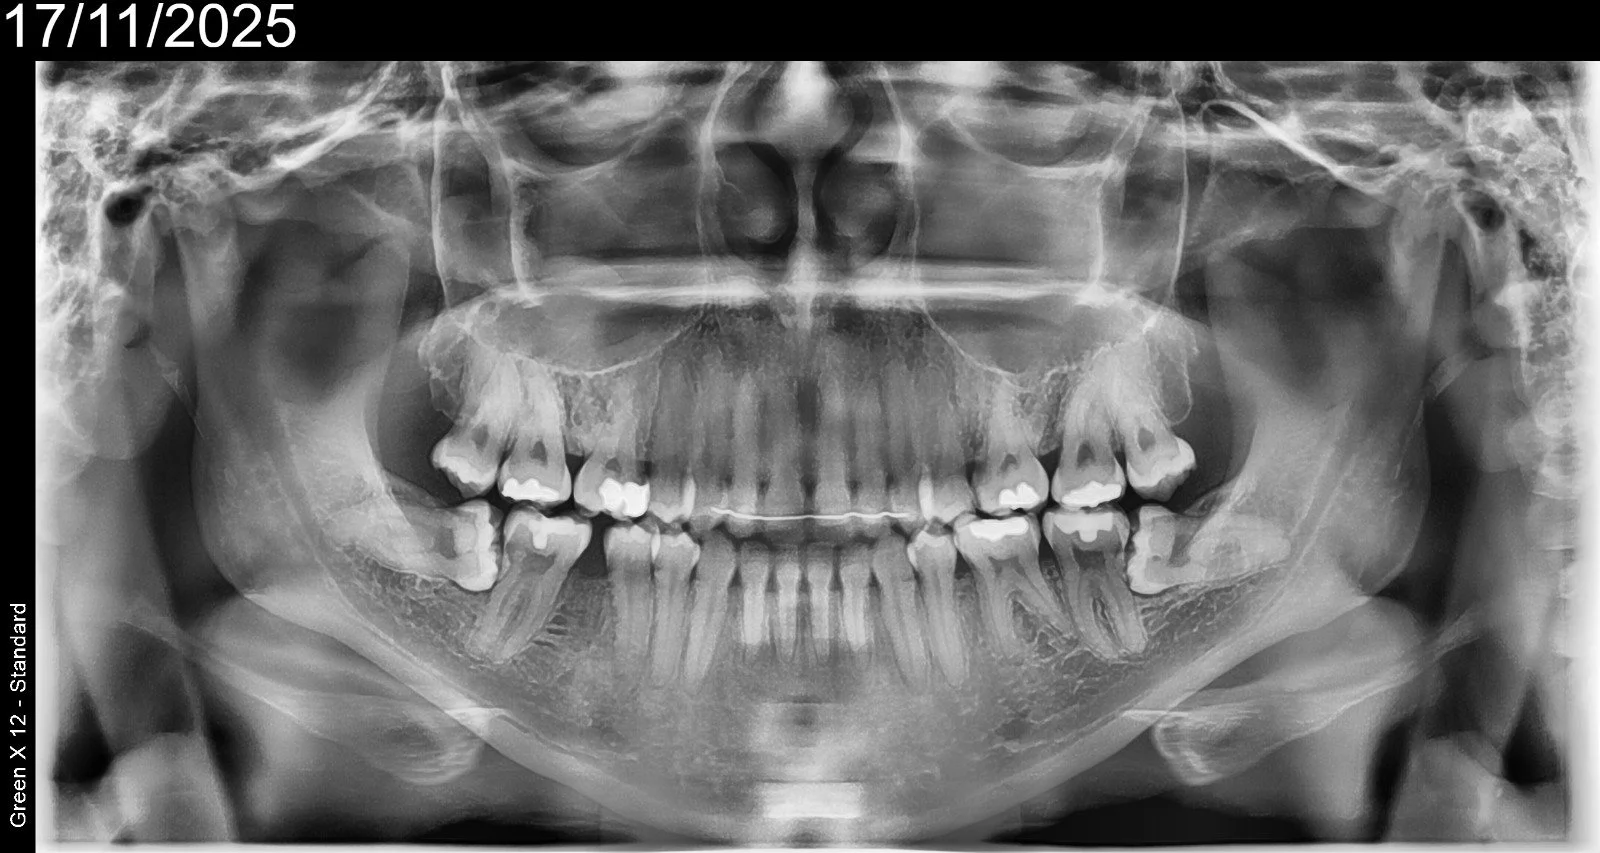

Class I Grade B

90 degrees root angulation

Severe decay. Tooth in 2 parts. Possible to save via hemisection.

Wisdom Tooth Class I Grade A and surgical removal of second molar.

Complicated Surgical Extraction of Upper Right Retained Roots

Complicated Surgical Extraction of Upper Left Retained Roots